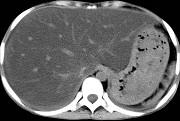

问题 男,57岁,肥胖、糖尿病、血脂升高,CT扫描如下图,请问诊断或描述错误的是哪一项 ( )

选项 A.肝硬化 B.脂肪肝 C.肝脏增大 D.密度均匀减低 E.血管影清唽可见

答案 A